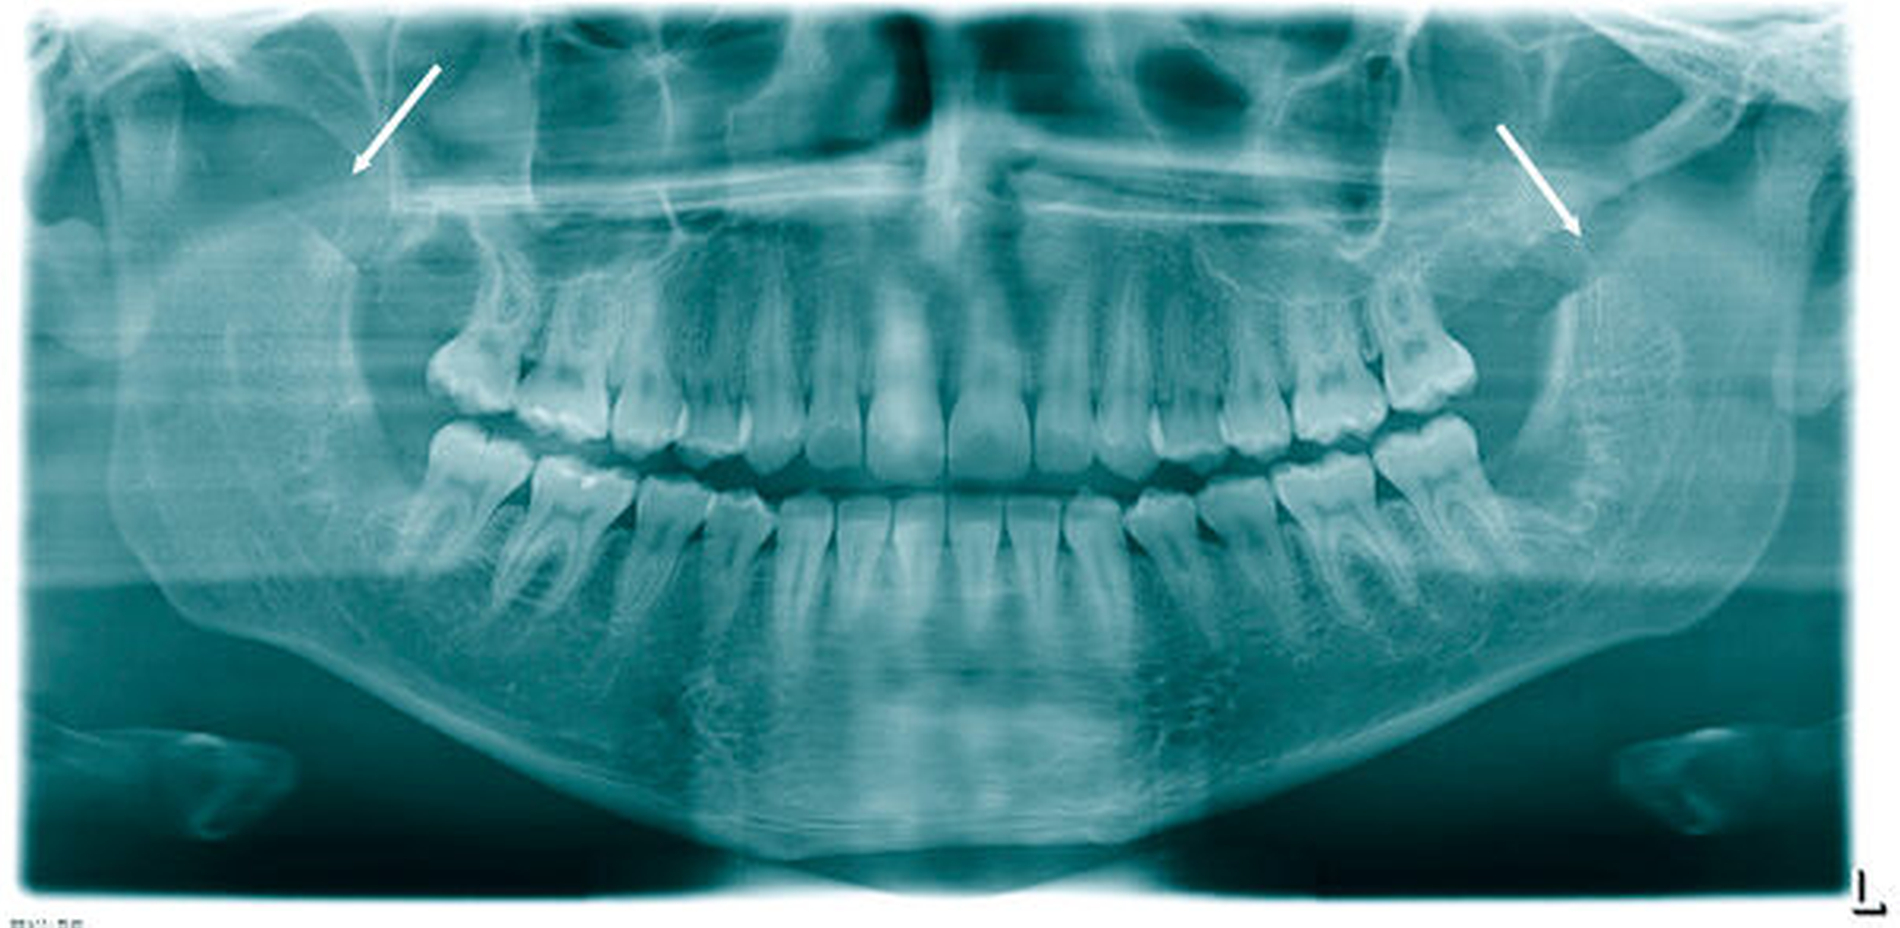

Der Patient erhielt daraufhin als konventionelle Röntgendiagnostik ein Orthopantomogramm (OPG). Hier bestätigte sich die Verdachtsdiagnose einer ausgeprägten, beidseitigen Elongation des Proc. coronoideus (Abbildung 2). Nebenbefundlich zeigten sich die vier Weisheitszähne retiniert.

Bei der Planung der Operation ist eine suffiziente Bildgebung unerlässlich. Das OPG sowie das dynamische OPG können bereits wichtige Informationen zu Länge und Form des Processus geben. Allerdings empfehlen wir zur genauen Darstellung von Länge, Breite, Struktur und Lage der anatomischen Nachbarstrukturen eine dreidimensionale Darstellung mittels CT oder DVT [Robiony et al., 2012]. Die dreidimensionale radiologische Diagnostik wird in der Regel vom MKG-Chirurgen bei entsprechendem Symptomkomplex (1. Mundöffnungseinschränkung, 2. keine Hinweise für eine Kiefergelenkspathologie, 3. Schmerzsensationen im Bereich des Jochbeins bei forcierter Mundöffnung, 4. keine Besserungstendenz nach initiierter konservativer Therapie) in die Wege geleitet [Kim et al., 2012].